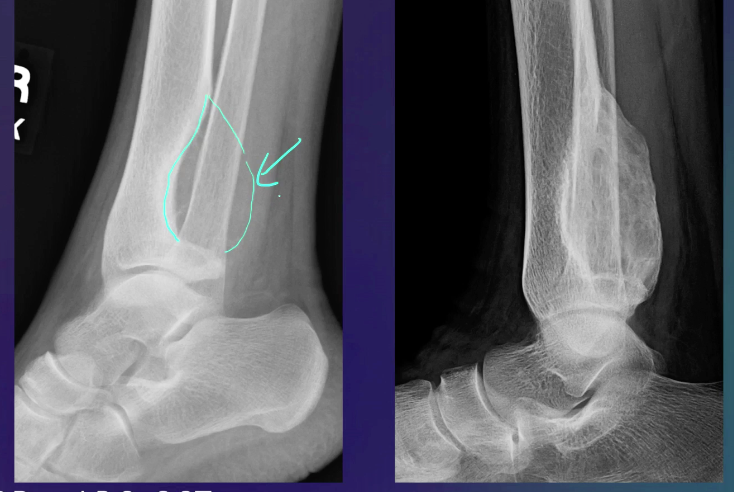

ABC